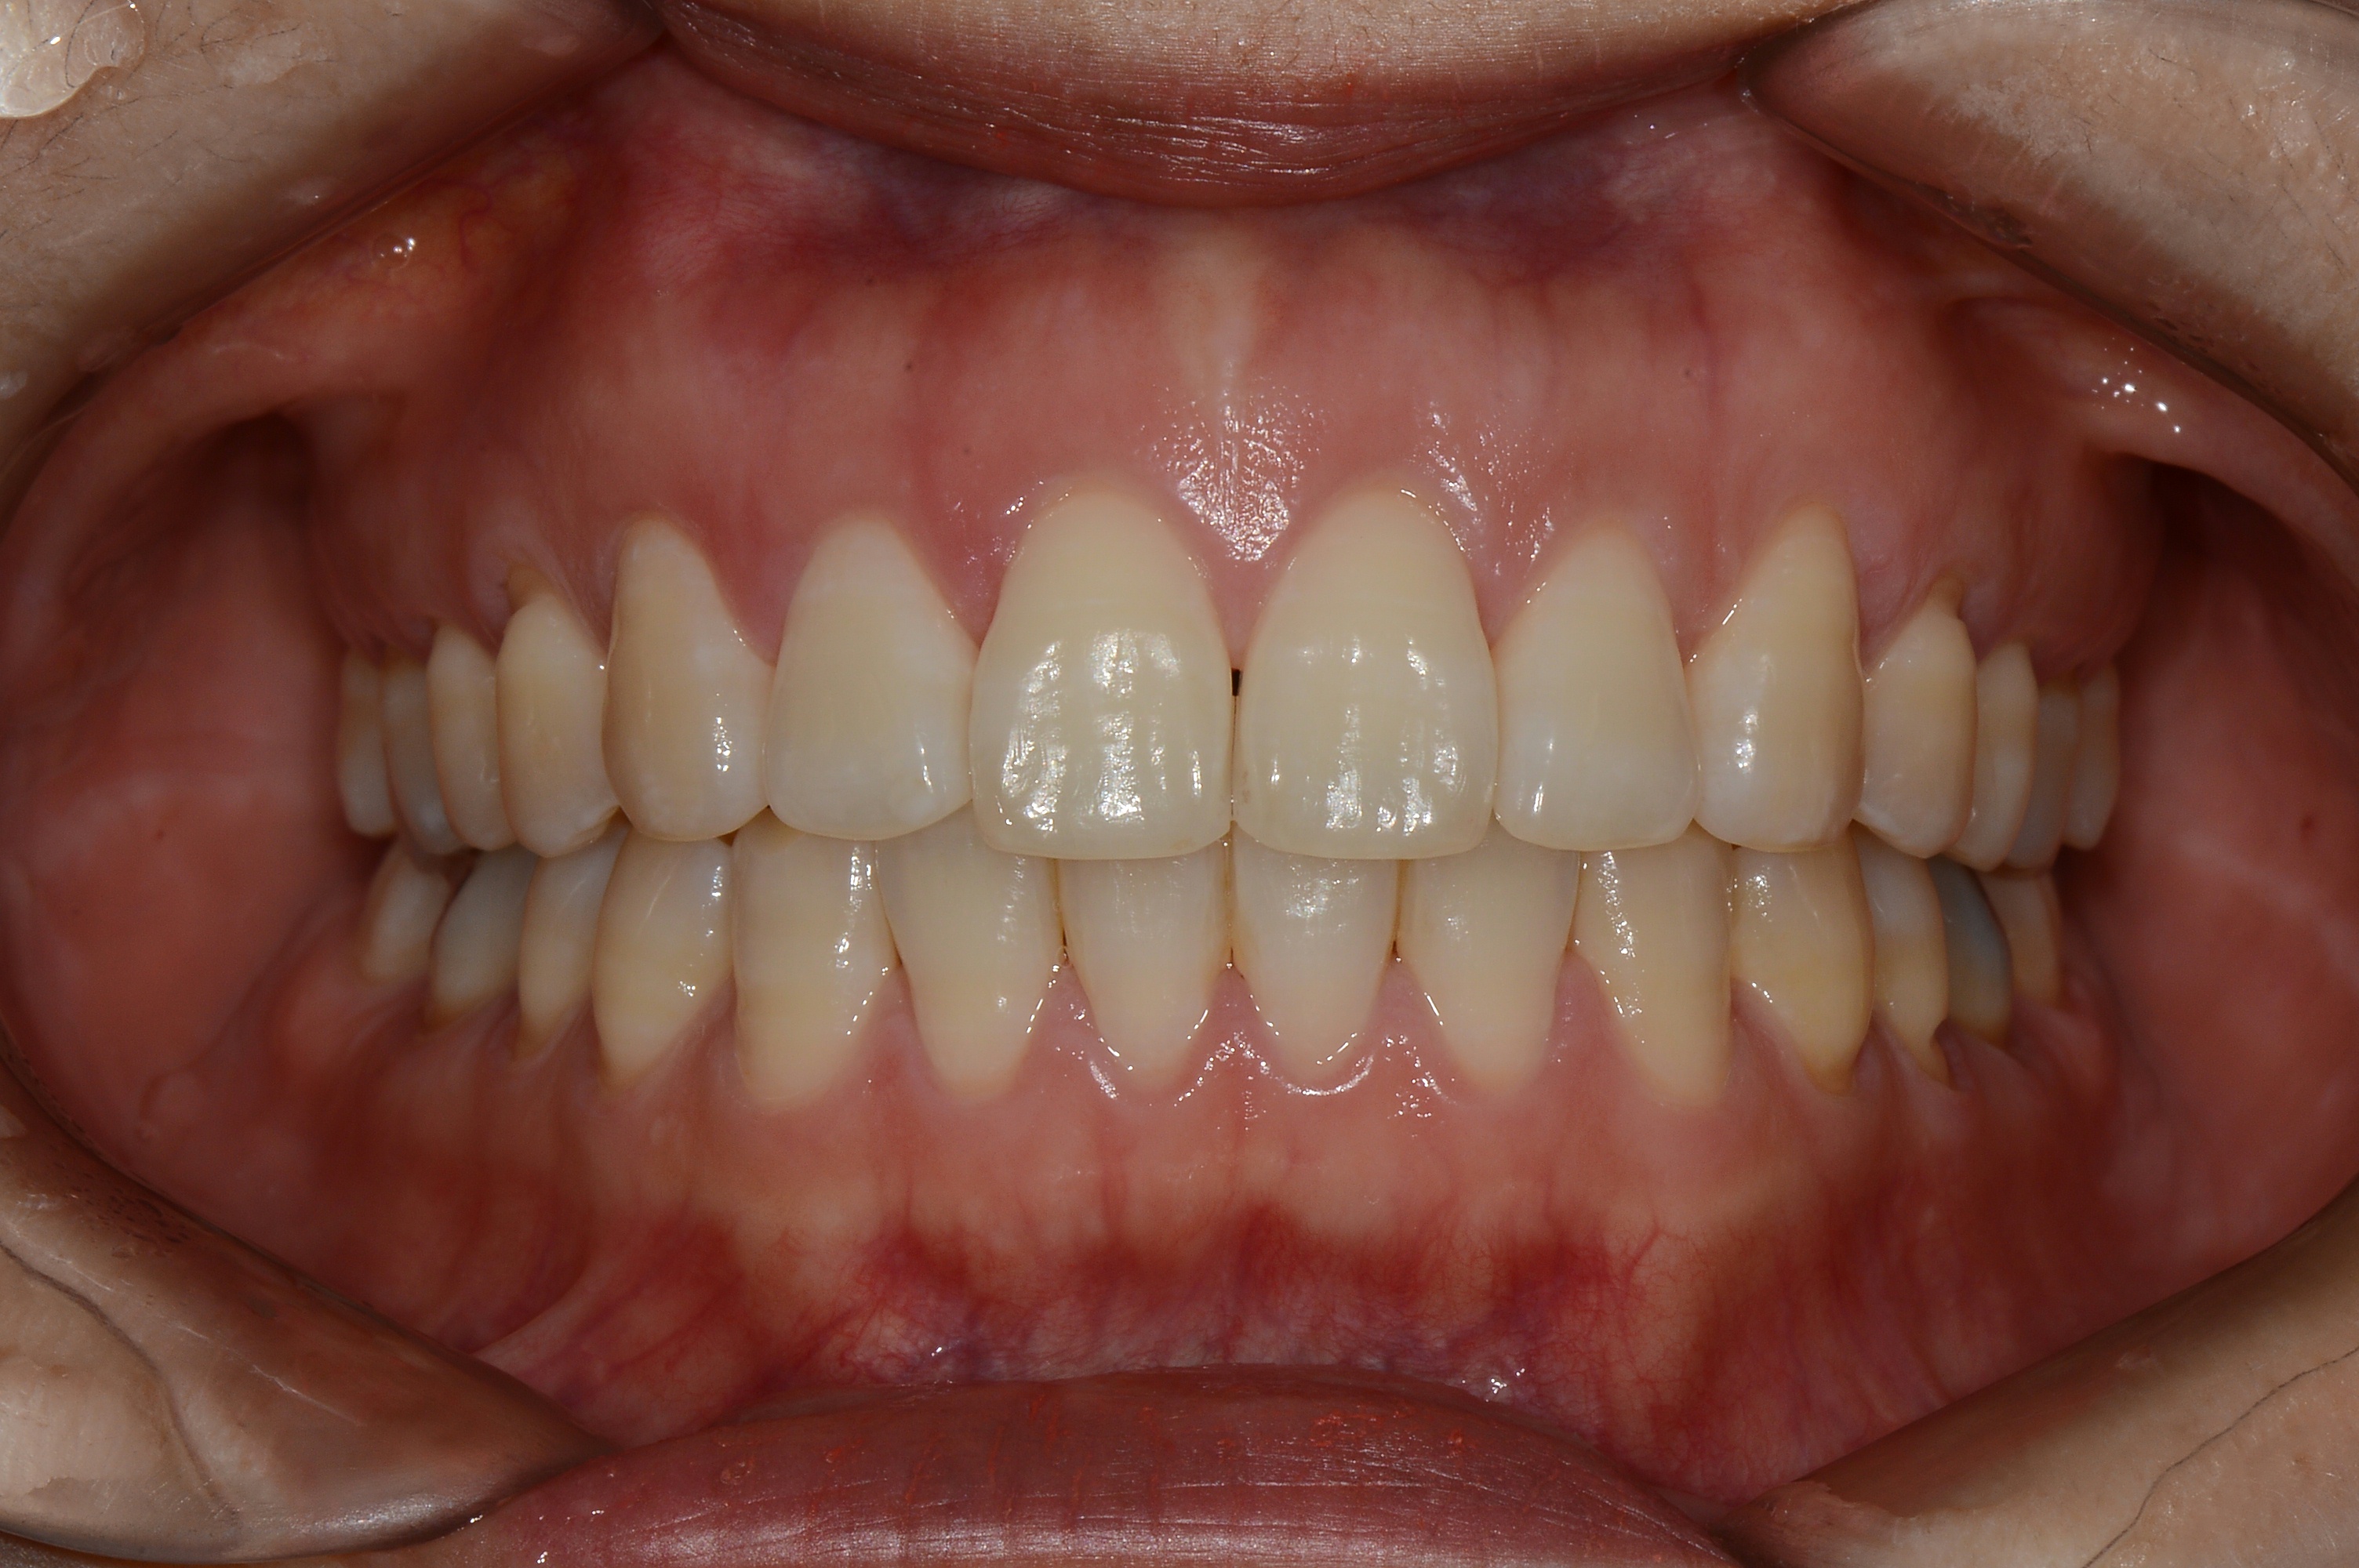

치료 전 사진입니다.